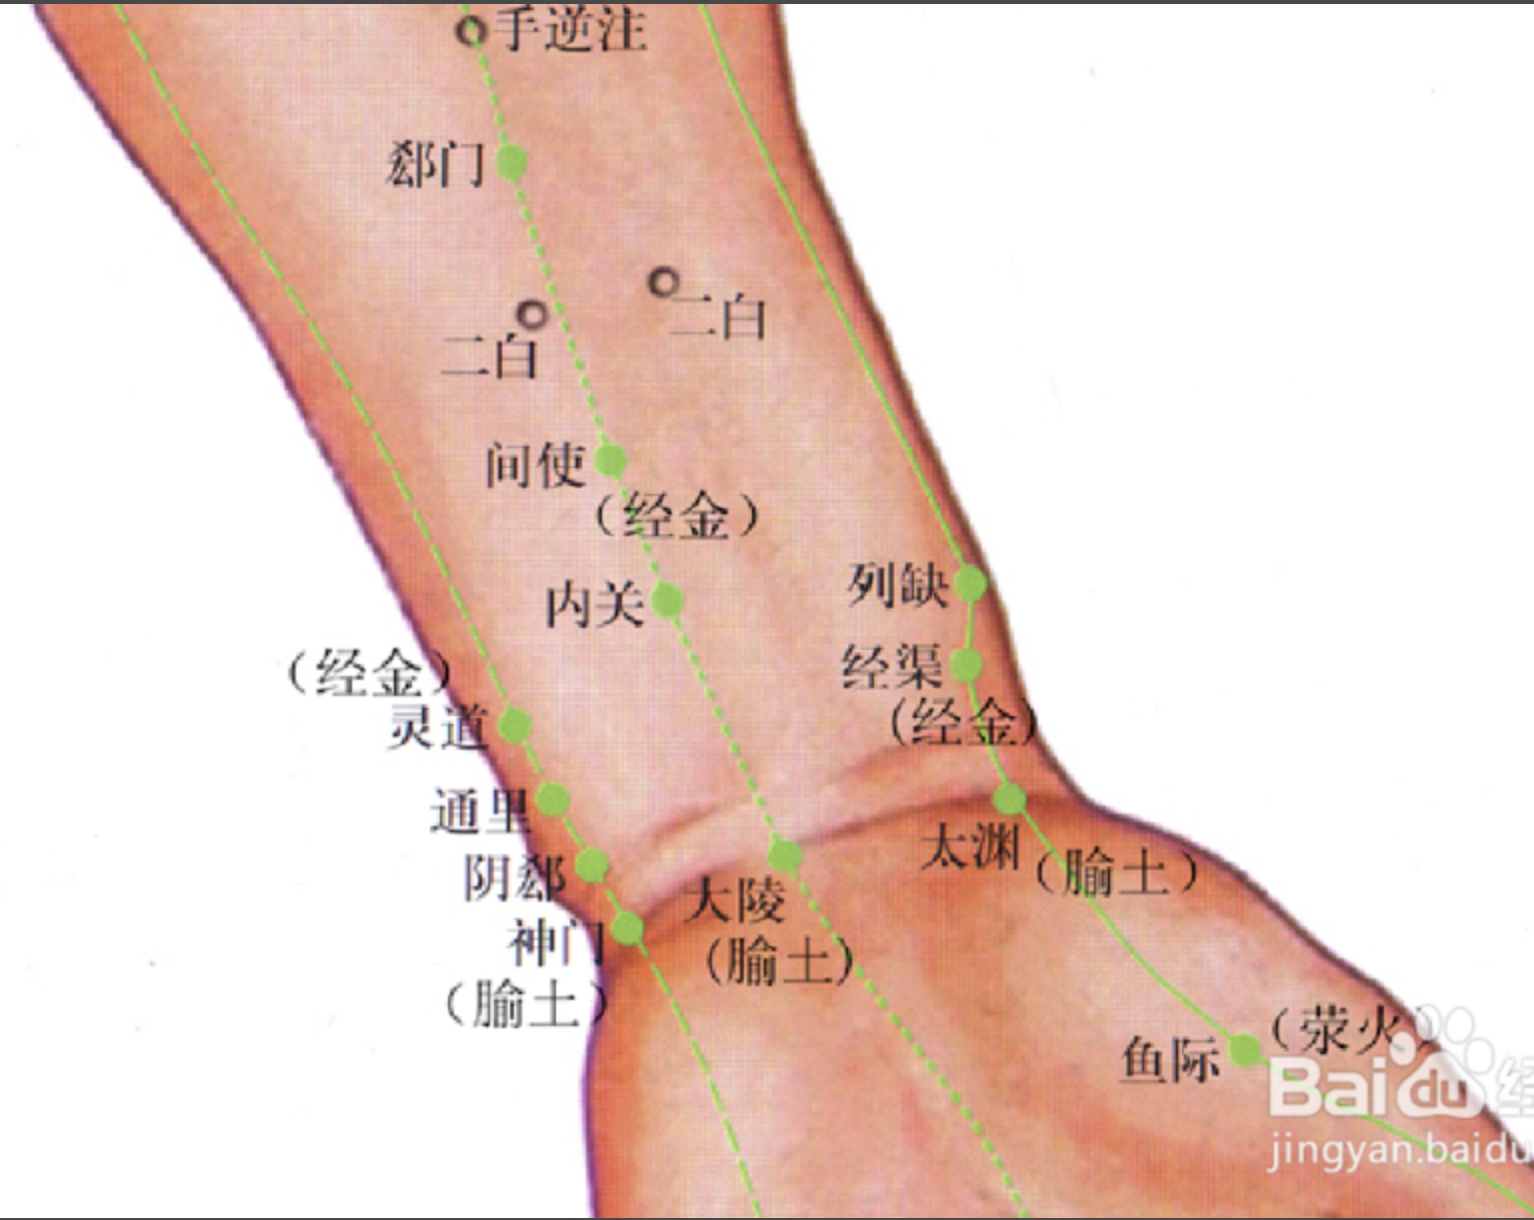

【(九)手厥阴心包经(图 10-27-1)】

2、歌诀 九穴心包手厥阴,天池天泉曲泽深,郄(xì)门间使内关对,大陵劳宫中冲侵。

曲泽

郗(xī)门

间使

内关